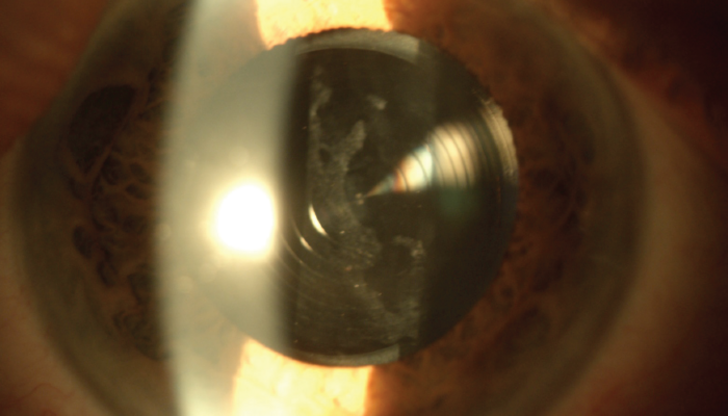

Premium lens cataract surgeries have transformed vision correction for millions globally, yet complications such as glare, halos, and blurry vision can leave some patients disappointed. Dr. Arun C. Gulani, a world-renowned eye surgeon, offers a groundbreaking, non-invasive approach to addressing these challenges by optimizing the cornea to work in harmony with the implanted lens. Learn how this innovative solution restores vision and exceeds patient expectations, all without going back under the knife.

Dr. Gulani’s method focuses on corneal optimization rather than invasive lens replacement, providing a non-surgical, effective solution for post-surgery vision complications.

Premium lens implants are just one ingredient in the overall “vision recipe.” By precisely reshaping the cornea to align with the lens, Dr. Gulani restores clarity while maintaining the integrity of the original surgery.

This technique is particularly effective for patients with prior LASIK, radial keratotomy, SMILE, PRK, or corneal crosslinking, addressing corneal abnormalities alongside vision correction.